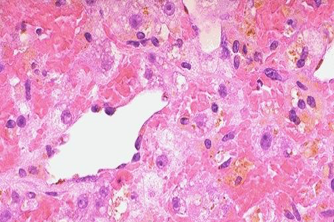

萎缩的器官体积变小,重量减轻,颜色变深或褐色如心和肝的褐色萎缩(brown atrophy)。光镜下实质细胞体积缩小或数目减少,间质出现纤维组织增生或脂肪组织增生。附图如下:

肝细胞萎缩 肝中央静脉的肝小叶中央区,由于缺氧细胞已萎缩或消失。萎缩 细胞胞质内可见棕黄色的脂色素颗粒堆积 |

心肌纤维萎缩 心肌纤维变细,细胞核缩小深染,萎缩心肌细胞核两端可见褐色脂褐素颗粒沉积 |

脂褐素(lipofuscin)又称老年素。沉积于神经、心肌、肝脏等组织衰老细胞中的黄褐色不规则小体,内容物为密度不等的物质、脂滴、小泡等,是溶酶体作用后剩下不再能被消化的物质而形成的残余体。脂褐素的积累随年龄增长而增多,是衰老的重要指征之一。见于浅表皮肤者俗称“老年斑”。